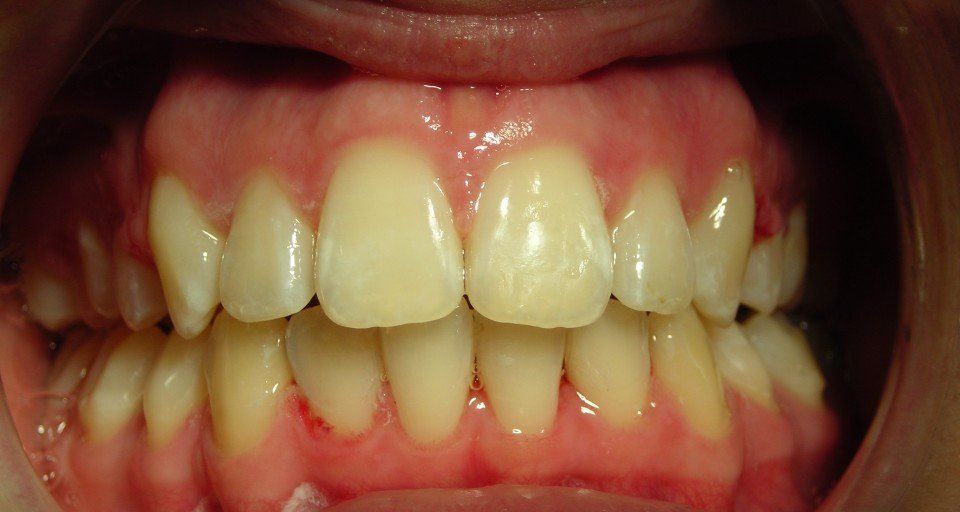

prima e dopo...

Trattamenti di parodontologia

La parodontologia è la branca dell'odontoiatria che si occupa dell'insieme dei tessuti molli (il legamento parodontale e la gengiva) e duri (cemento e tessuto osseo alveolare) che circondano il dente e che assicurano la sua stabilità nell'arcata alveolare. Cura le malattie che interessano il parodonto, chiamate genericamente malattie parodontali o parodontopatie: sono le parodontiti e le gengiviti.

Nel nostro studio abbiamo a cuore la prevenzione delle patologie oro-dentali e la nostra specialista igienista promuove la salute orale dei pazienti al fine di migliorarne anche la salute sistemica, nonché l'estetica e l'autostima. La parodontologia riveste un ruolo importante nella terapia non chirurgica di mantenimento dei pazienti con malattia parodontale.